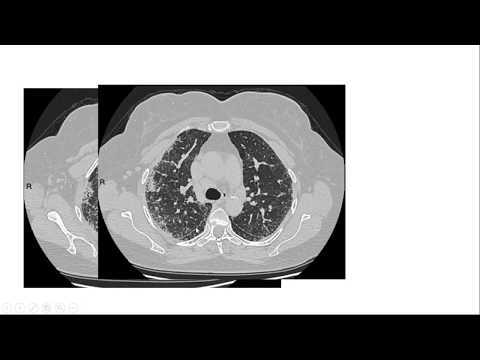

11:30 TAC de tórax en COVID-19: clásico, inusual, muy raro Santiago Rossi